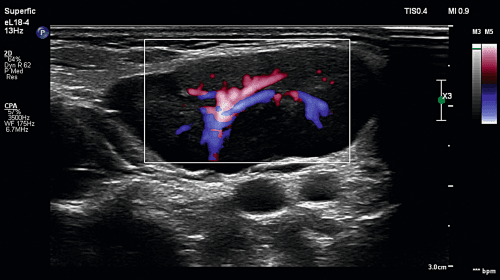

Chłopiec 10-letni został przyjęty z powodu utrzymującej się od 3 dni gorączki do 39°C z towarzyszącymi bólami brzucha oraz wymiotami. Przy przyjęciu w badaniu fizykalnym z odchyleń od normy zaobserwowano powiększone węzły chłonne szyjne i podżuchwowe, zaczerwienienie gardła; brzuch był miękki, nieco tkliwy przy palpacji w nadbrzuszu środkowym. W badaniach laboratoryjnych stwierdzono: w morfologii krwi obwodowej przewagę limfocytów, podwyższenie transaminaz oraz nieznaczne narastanie parametrów stanu zapalnego (OB, CRP, PCT). W wykonanym badaniu ultra-sonograficznym jamy brzusznej – hepatosplenomegalia. W USG szyi uwidoczniono obustronne odczynowe powiększenie węzłów chłonnych (największy po stronie prawej do 42 x 15 mm). Węzły chłonne w tym przypadku były zmienione zapalnie i cechowały się w badaniu ultrasonograficznym zwiększonym wymiarem, ale zachowanymi proporcjami (kształt owalny), zatartą wnęką, nieco zmniejszoną echogennością części obwodowej oraz zwiększonym odwnękowym unaczynieniem. Węzły te układały się w postaci konglomeratów – widoczne były wyraźne granice między poszczególnymi węzłami chłonnymi (w odróżnieniu od pakietów). W badaniach mikrobiologicznych uzyskano dodatnie miano przeciwciał w kierunku EBV VCA/EA IgM oraz EBV VCA/EA IgG. Rozpoznano mononukleozę zakaźną. Zastosowano leczenie objawowe. W tym przypadku był to obraz ostrego zapalenia węzłów chłonnych. W przebiegu przewlekłego zapalenia węzły limfatyczne różnią się od prawidłowych jedynie wielkością (są większe), a unaczynienie nie jest tak obfite jak w stanach ostrych. Węzły chłonne prawidłowe oraz odczynowe mają niskooporowe spektrum przepływu RI < 0,7.